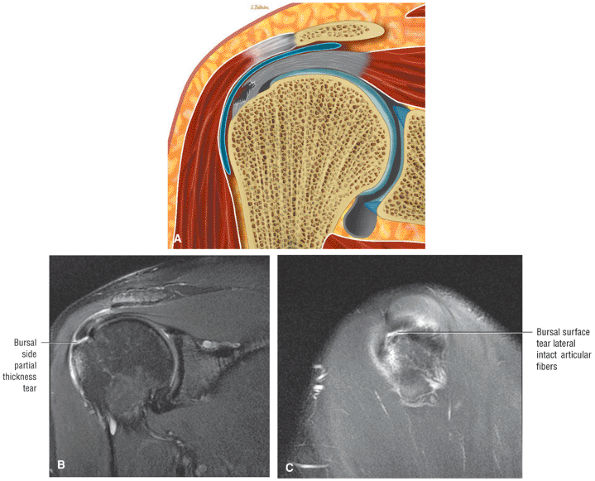

FIGURE 8.102 ● (A) The anterior undersurface of the acromion and the coracoacromial ligament form the coracoacromial arch. The subacromial subdeltoid bursa facilitates the passage of the rotator cuff and proximal humerus under the coracoacromial arch. (B) A superior axial image shows the anterior-to-posterior extent of the coracoacromial (CA) ligament perpendicular to the supraspinatus tendon. The fluid in the subacromial-subdeltoid bursa represents fluid between two serosal surfaces in contact with each other. One serosal surface is contributed by the undersurface of the coracoacromial arch and deltoid, and the other serosal surface is on the bursal side of the cuff.

|

![]() |

FIGURE 8.103 ● Pseudospur. The normal broad attachment of the coracoacromial ligament to the inferior surface of the acromion is shown on (A) T1-weighted coronal oblique and (B) sagittal oblique images. The low-signal-intensity acromial cortex (black arrows) and adjacent coracoacromial ligament and lateral slip of the deltoid attachment (white arrows) give the false impression of a small subacromial spur in the coronal plane. This pseudospur should not be misinterpreted as impingement; otherwise, unnecessary acromioplasties may be performed on patients with a normal coracoacromial ligament attachment and no associated acromial spurs.

-

Impingement syndrome, a clinical diagnosis, is characterized by a range of MR findings from tendinosis to rotator cuff tears.

Intrinsic impingement is associated with shoulder instability.